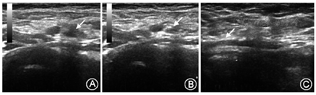

16例患儿因坏死性小肠结肠炎合并多器官衰竭死亡2例,死亡时间分别为置管后35 d和66 d;4例电话随访,10例门诊随访,中位随访时间622(22~1 082) d ,门诊随访病例均行穿刺部位彩超检查。所有随访患儿两侧下肢对称,无水肿、感觉或运动障碍等异常;彩超复查2例右股静脉穿刺患儿出现穿刺处血管轻度狭窄(图1);1例右股静脉出现中度狭窄,表现为局部管壁增厚,管径减小(图2)。其中,深静脉中度狭窄患儿置管术耗时95 min,导管留置时间为19 d;余患儿相应部位深静脉血流均通畅,无静脉血栓形成。

新生儿静脉细,直接穿刺是否会造成远期狭窄或闭塞是目前关注的问题。穿刺血管狭窄及栓塞的发生率随穿刺次数增多、导管留置时间过长而增高[20,21]。本组病例出院时(包括2例死亡患儿)穿刺部位与穿刺侧肢体体格检查均无异常,随访时彩超复查穿刺处深静脉有3例(3/10)出现轻-中度狭窄,表现为局部管壁增厚、管径减小,但血流通畅,远期预后还有待随访。